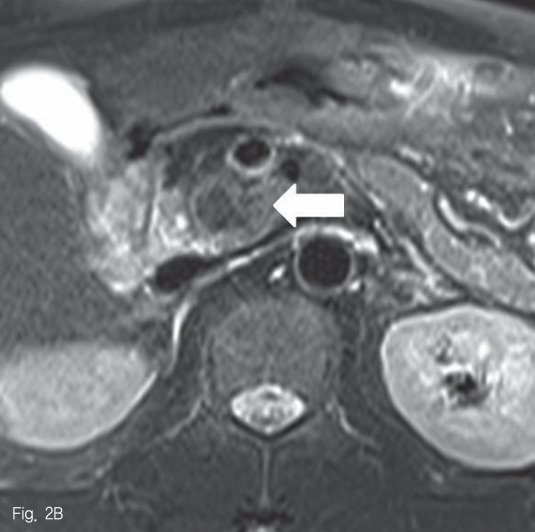

초음파 검사에서 췌장 두부에 약 2.5cm 크기의 종괴가 있었다 (Fig. 1). 췌장 자기공명영상에서 종괴는 T1-weighted image에서 다양한 신호강도를 보였고, T2-weighted image 에서는 저신호강도를 보여 다양한 단계의 출혈을 포함한 병변으로 생각하였다 (Fig. 2A-B). 조영 증강 자기공명영상 및 조영 증강 복부 전산화단층촬영에서 종괴의 내측으로 혈관과 비슷한 조영 증강을 보이는 1cm 크기의 병변이 보여 가성동맥류로 진단하였다 (Fig. 2C-D).

Fig 2B

Pancreatic MRI reveals a mass in pancreatic head. It shows heterogeneous signal intensity in T1-weighted image (A, arrow) and low signal intensity in T2-weighted image (B, arrow).